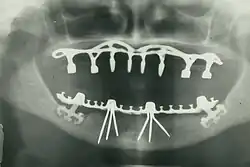

Můstek podepřený implantátem (nebo fixní zubní náhrada) je skupina zubů upevněných na zubních implantátech, takže uživatel nemůže protézu sundat. Jsou podobné běžným můstkům s tím rozdílem, že protéza je podepřena a upevněna jedním nebo více implantáty namísto přirozených zubů. Můstky se obvykle připojují k více než jednomu implantátu a mohou se také připojovat k zubům jako kotevní body. Obvykle počet zubů převyšuje počet kotevních bodů, přičemž zuby, které jsou přímo nad implantáty, se označují jako pilíře a zuby mezi pilíři se označují jako mezičleny. Můstky podporované implantáty se připevňují k pilířům stejným způsobem jako náhrada jednoho zubu implantátem. Fixní můstek může nahradit i pouhé dva zuby (známý také jako fixní částečná zubní náhrada) a může se rozšířit a nahradit celý zubní oblouk (známý také jako fixní úplná zubní náhrada). V obou případech se o protéze říká, že je fixní, protože ji nositel nemůže sundat.[12]